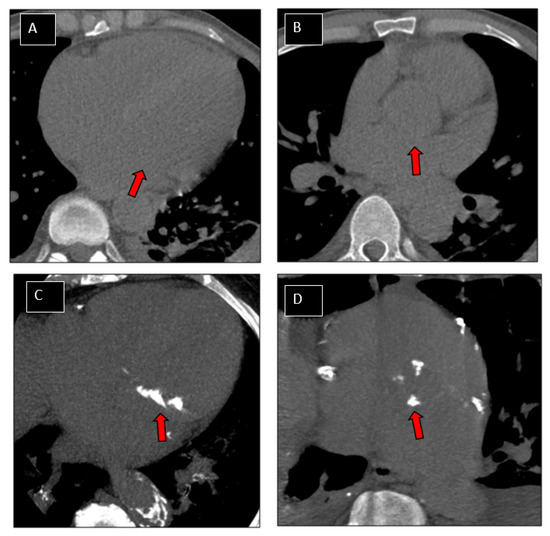

3.2.1. Patients with Native Mitral IE

3.2.2. Patients with Native Aortic IE